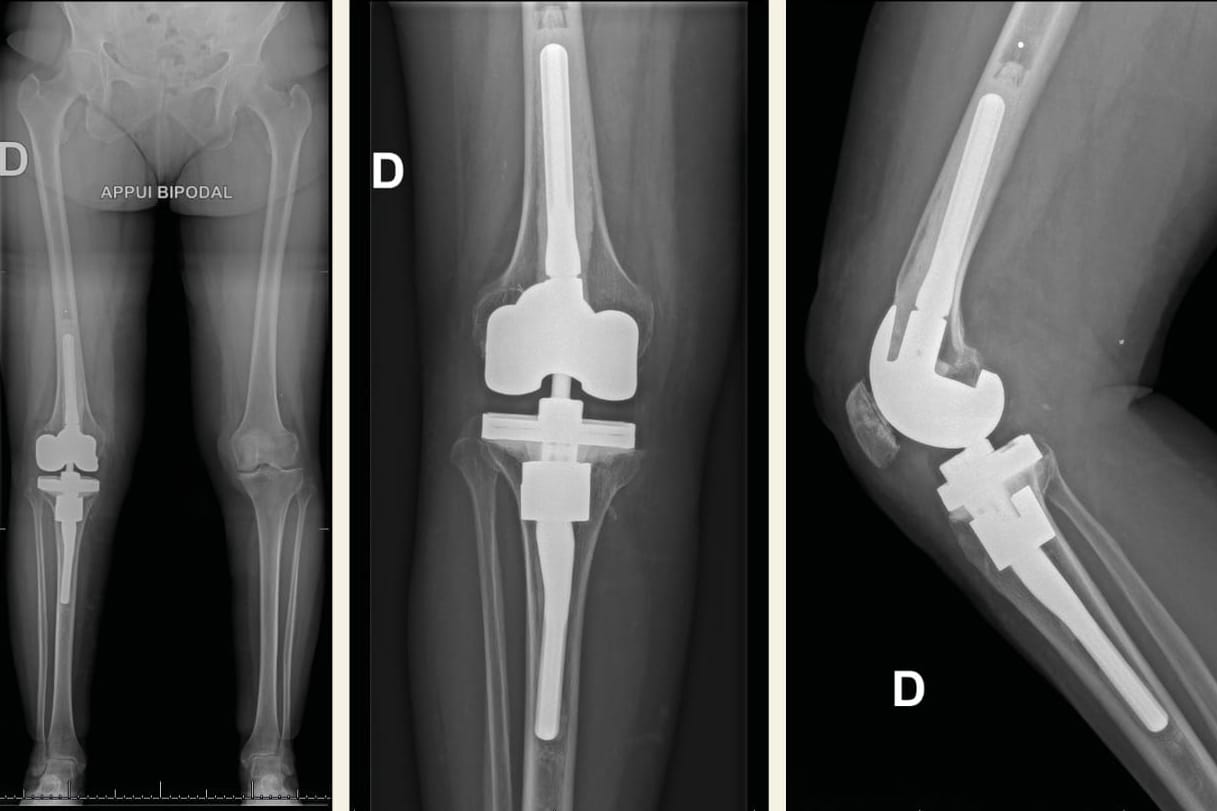

Évolution des ions métalliques après implantation d’une prothèse de genou